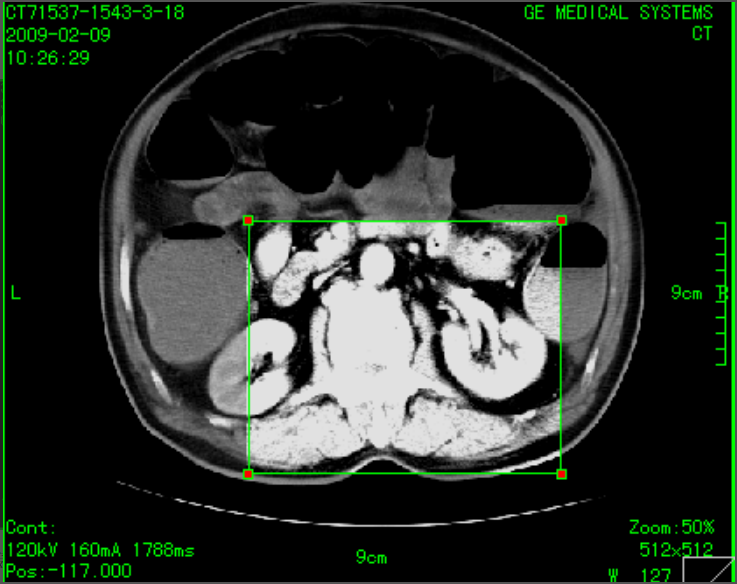

二维图像处理:支持图像无级缩放、图像旋转、翻转、图像移动漫游、图像黑白翻转、伪彩、放大镜、图像复制、窗宽、窗位调节、预设窗宽/窗位、ROI自动窗宽、窗位调节、窗宽、窗位曲线调节、显示双窗宽/窗位、测量、标记、距离测量、角度测量、椭圆测量、任意形状面积测量、文字注释、图形、箭头标注、可手画线、长度、面积计算显示、ROI平均密度值测量:圆形、矩形等、图像拼接、图像增强、心胸比测量;

三维可视化系统:MPR多平面重建、CPR曲面重建、MIP最大密度投影、MinIP最小密度投影、VR体积重建、CalSCore心脏图像冠脉钙化积分、VE虚拟内窥镜